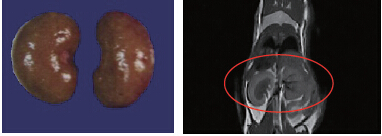

44.8g小鼠,腎臟體積:0.315cm3,解剖體積(水溢法):0.293cm3,成像時(shí)間:10min